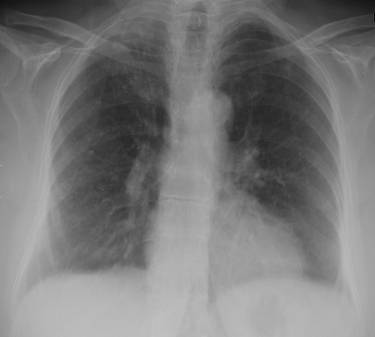

Imagen malapraxis-pulmonia

Los camaristas consideraron probada la “conducta omisiva” que cuando atendió a la joven, la profesional al limitarse a interrogarla, y “palpar la zona del pecho, sin auscultarla, y interpretar ligeramente el análisis de laboratorio, omitiendo la realización de placas radiográficas y nuevos estudios que permitieran determinar adecuada y temporariamente el cuadro que presentaba la joven y prescripción de un equivocado tratamiento, (medicación incorrecta, tratamiento ambulatorio, etc.) que tuvo como consecuencia el desenlace fatal constituye la mala praxis”.

Cabe recordar que la víctima concurrido en tres ocasiones a la clínica. La primera el 24 de diciembre y luego 4 días después, cuando fue atendida en el mismo día en dos ocasiones. La segunda, de las tres veces en que fue atendida, la médica imputada al atenderla “miró el análisis y dijo que se trataba de una falsa alarma” recetándole vitaminas y un tranquilizante, cuando en realidad la joven estaba padeciendo una severa infección respiratoria y sólo le funcionaba la cuarta parte de un solo pulmón.